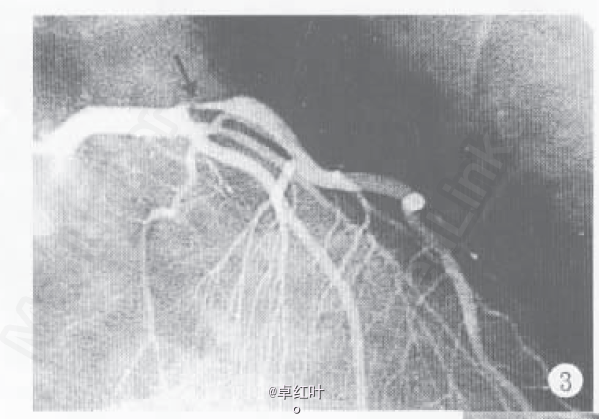

诊断:冠心病,陈旧下壁心肌梗死,劳累恶化型心绞痛; 处理:冠脉造影+支架植入术。